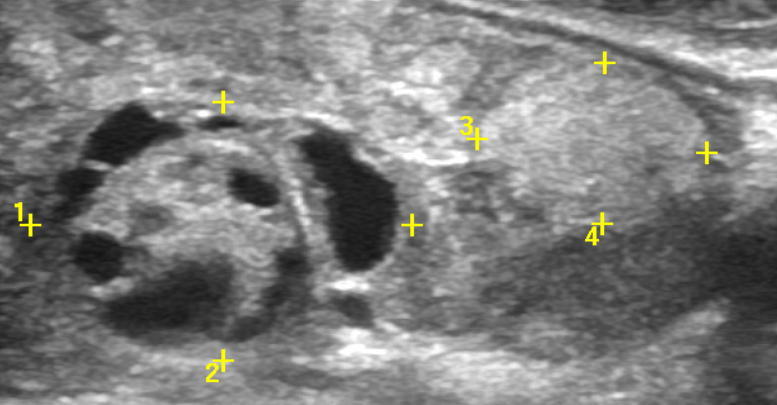

Теплый узел щитовидной

Теплый узел щитовидной 107 фотографий